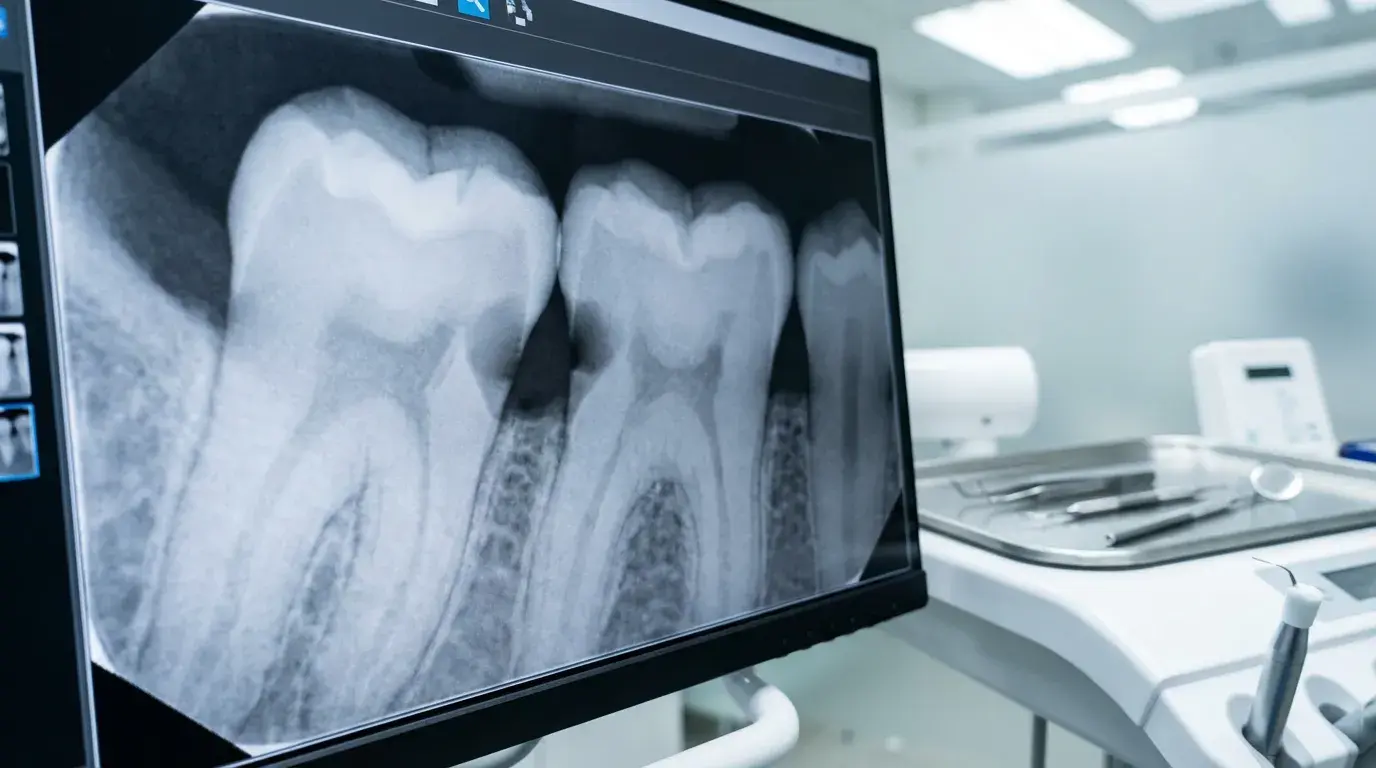

충치 진단 시 엑스레이 판독 팁으로는, 상아질까지 진행된 병소는 명확하게 보이지만 법랑질 손상과 충치 진행 초기 단계는 영상에서 잘 구분되지 않는다는 점을 기억해야 해요. 따라서 방사선 사진에 병소처럼 보이더라도 실제로는 와동이 아닐 수 있습니다. 인접 면 충치 엑스레이 판독 시에는 바이트윙(Bitewing) 촬영을 활용해 치아 사이 진행 여부를 정확히 확인하며, 인접 면 충치 진행 속도가 빠른 경우 6개월 주기로 정기 점검하는 것이 권장됩니다. 내부 충치(속충치) 증상 및 진단은 겉으로 보이지 않기 때문에 엑스레이가 특히 중요한 역할을 하죠.

이런 증상이 있다면 인접 면 충치 증상 및 진단을 위해 치과 엑스레이로 보는 충치 검사(바이트윙 촬영)를 받아보세요. 인접 면 충치 엑스레이 판독을 통해 겉으로 보이지 않는 내부 충치(속충치) 증상도 조기에 발견할 수 있습니다.

충치 진행 속도는 겉으로 드러나지 않아도 치아 내부에서 조용히 진행되기 때문에, 적시에 정확한 진단을 받는 것이 무엇보다 중요해요. 치과 엑스레이로 보는 충치 검사는 내부 상태를 파악하는 핵심 도구지만, 엑스레이 영상만으로는 모든 단계의 충치를 완벽하게 판별하기 어렵습니다. 그래서 치과에서는 육안 관찰(시진), 탐침 검사, 방사선 촬영을 종합적으로 활용해 치과에서 충치 단계 판정 기준을 적용하고 있어요.